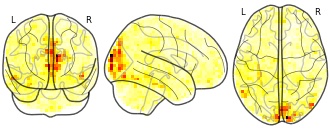

Movie clips: importance map LRP 5 Sadness

niftiUpdated Jan 9, 2018+ more versions Share

EmailClick to copy linkLink copied Cite(2018). Movie clips: importance map LRP 5 Sadness [Dataset]. http://identifiers.org/neurovault.image:58829niftiAvailable download formatsUnique identifierhttps://identifiers.org/neurovault.image:58829Dataset updatedJan 9, 2018License

Cite(2018). Movie clips: importance map LRP 5 Sadness [Dataset]. http://identifiers.org/neurovault.image:58829niftiAvailable download formatsUnique identifierhttps://identifiers.org/neurovault.image:58829Dataset updatedJan 9, 2018LicenseCC0 1.0 Universal Public Domain Dedicationhttps://creativecommons.org/publicdomain/zero/1.0/

License information was derived automaticallyDescription - a